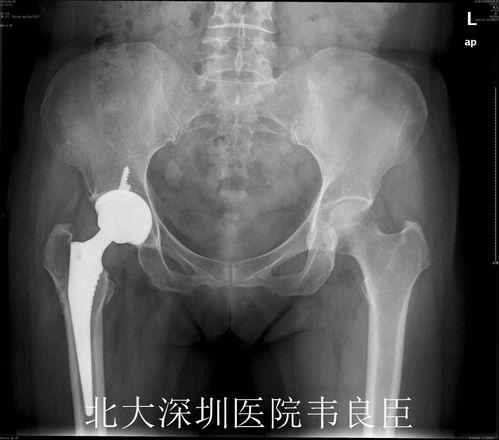

在手术之前,医生会为你进行一系列的检查,以确保手术的顺利进行。这些检查包括但不限于X光、CT扫描和血液检查。通过这些检查,医生可以了解你的髋关节状况,评估手术的可行性。

置换股骨头手术通常分为两个部分:股骨头置换和髋臼置换。下面,我们就来详细了解一下手术过程。

首先,医生会在患者的髋关节处切开一个小口,然后取出坏死的股骨头。接着,医生会植入一个新的股骨头,这个股骨头通常由金属制成,具有良好的生物相容性。

视频中,我们可以看到医生正在小心翼翼地取出坏死的股骨头,并植入新的股骨头。手术过程中,医生需要确保新股骨头与髋臼紧密贴合,以恢复髋关节的正常功能。

在完成股骨头置换后,医生会继续进行髋臼置换。首先,医生会在髋臼处切开一个小口,然后取出坏死的髋臼部分。接着,医生会植入一个新的髋臼,这个髋臼通常由陶瓷或金属制成。

视频中,我们可以看到医生正在为患者植入新的髋臼。手术过程中,医生需要确保新髋臼与股骨头紧密贴合,以恢复髋关节的正常功能。